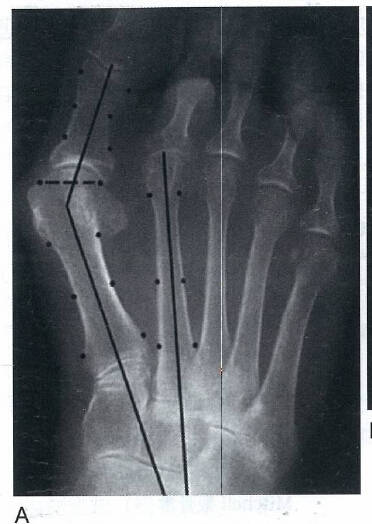

拇外翻的病因:

遗传、性别、生活习惯、关节疾病等因素

拇外翻病理改变:

病变发生在第一跖趾关节

第一跖骨内翻,跖骨头向内移位,而籽骨在拇收肌、拇短屈肌和跖横韧带等结构的牵拉下维持原位,籽骨相对于跖骨头向外发生移动,跖骨头跖侧骨嵴被磨平籽骨失去了跖趾关节在屈伸中的滑车作用,籽骨的外移将会牵拉拇趾近节趾骨发生旋转。

其他两个涉及第一跖趾关节的解剖学改变也可以引起拇外翻

第一个改变为跖骨头关节面偏斜,其偏斜的角度被称为跖骨远端关节固角(DMAA)

第二个改变为趾近节趾骨基底的关节角相对于其纵轴出现偏斜,其偏斜角度被称为趾骨近端关节固角(PAA)